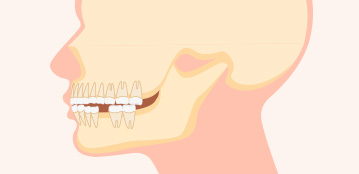

앞니 돌출

잇몸 뼈는 정상이나

앞니 치아가 튀어나온 경우